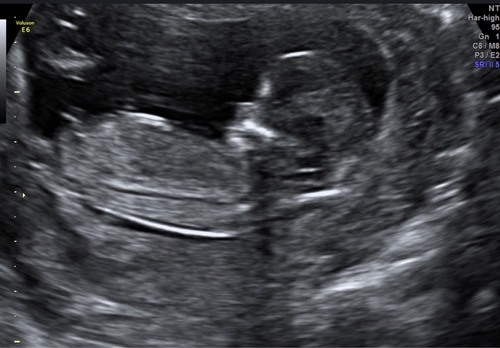

@nubster Net 13 weken echo gehad, wat denk jij? 🥰

Hier denk ik 💙 had je eerder een andere foto geplaatst?